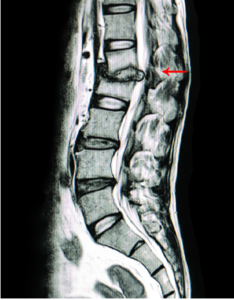

Lumbar Disc Herniation

Lumbar disc herniation is the most common cause of low back pain and leg pain (sciatica). The lumbar intervertebral discs are flat and round.

Lumbar Radiculopathy

Back pain is a common condition affecting approximately 80% of the population at some point in their lives. The area usually affected is the lower back…